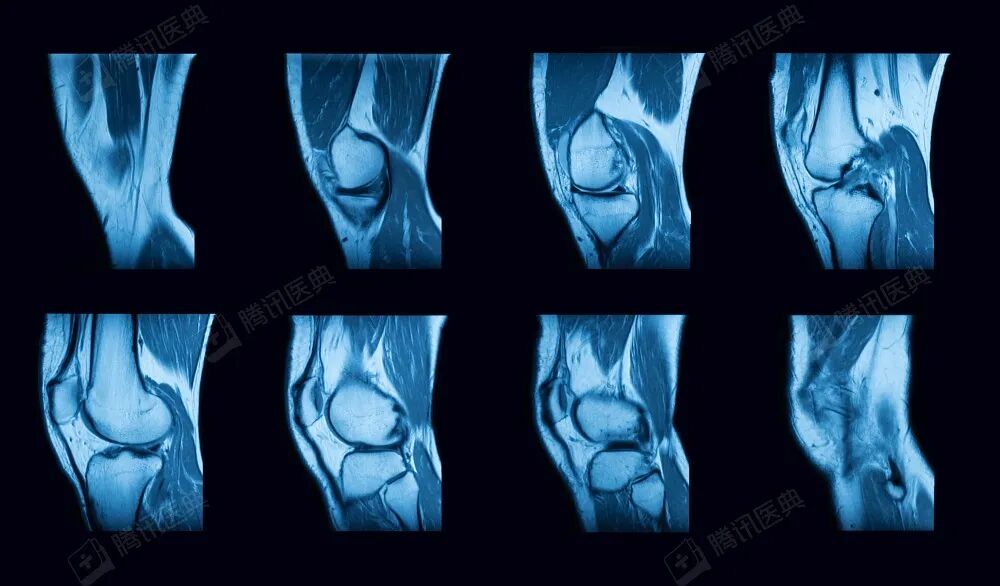

两人急忙带着松松赶到南昌,但医院做核磁共振要排队十多天,他们等不及,又马不停蹄赶到上海复旦大学附属肿瘤医院,经过检查,确诊右下肢骨肉瘤。

为了做肿瘤切除手术,松松先得做三期化疗。可喜的是化疗见效,肿瘤明显缩小,以前肿瘤部位鼓鼓的,化疗后那片皮肤变得皱巴巴的,像漏了气的气球。

幸运的是,手术很成功,松松的腓骨被切掉,置换了半个膝关节,再重建血管、接上神经,手术中输了2600毫升血,松松切下来的骨头是黑的。